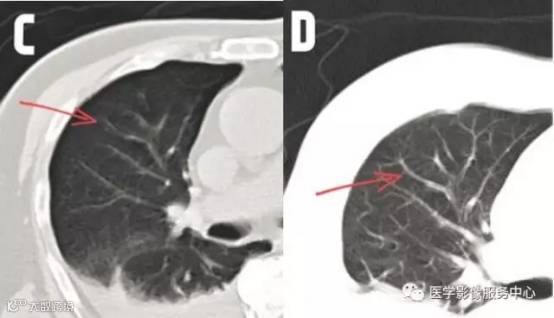

那为什么需要重扫呢?因为患者在扫描过程中由于气没有屏住,产生的呼吸运动,导致图像模糊。和拍照片的原理一样,拍照片的时候,人动了,照片就糊了。打一个比方,当我们拍照的时候,在按下快门的瞬间手抖了一下,拍出来得照片就会模糊不清,旁人无法从中得知照片上的人是谁。原理一样,倘若做CT 的时候气没有憋住,出来的图像会有重叠,模糊等现象,严重影响图像的质量,有碍诊断。

图C: 箭头处有明显叠影 图D: 箭头处无明显叠影